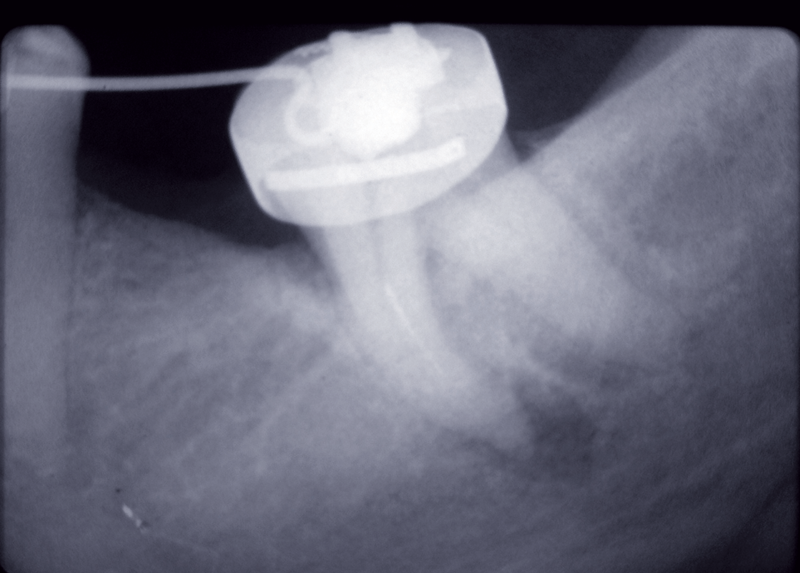

Traitement endodontique

Le système canalaire, source de l’infection, doit être nettoyé par une préparation chimio-mécanique complète en prenant soin d’éviter toute surinstrumentation irritante pour les tissus péri-apicaux et pouvant contribuer à projeter des débris contaminés dans la zone péri-apicale. En effet, la surinstrumentation peut déclencher une flambée infectieuse ou « flare up ».

L’utilisation de la technique « crown down » couplée à une irrigation abondante à l’hypochlorite de sodium ainsi que…